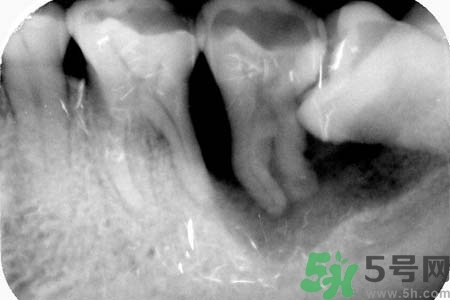

如果發(fā)現(xiàn)自己的智齒橫著長(zhǎng)了,為了不讓智齒阻生引起其他的危害,我們一定要盡快把橫著長(zhǎng)的智齒拔除,而且不需要鑲牙,拔掉之后有助于身體健康,還可以保護(hù)附近其他牙齒。但是,我們還要重視一點(diǎn),拔智齒是一種牙科門診手術(shù),要求醫(yī)生的技術(shù)水平要比較高,因?yàn)闄M生的智齒,拔除的時(shí)候難度更大,首先要將黏膜切開(kāi),去骨之后才可以拔除的,這不是普通的牙醫(yī)可以把握好的。所以,小編在此提醒各位患者,務(wù)必選擇正規(guī)的牙科醫(yī)院,由專業(yè)的牙科醫(yī)生進(jìn)行拔除手術(shù)。

智齒橫著長(zhǎng)在拔除的時(shí)候需要遵循一些原則。正常情況下,生長(zhǎng)情況沒(méi)有出現(xiàn)異常的智齒盡量要保留下來(lái),不要隨便進(jìn)行拔除。特別是那些生長(zhǎng)了很多年的智齒。只有當(dāng)智齒非正常生長(zhǎng),出現(xiàn)一些臨床癥狀的時(shí)候,才有拔除的需要。而且,在進(jìn)行拔除手術(shù)之前,一定要先拍攝牙片,確定智齒生長(zhǎng)異常再進(jìn)行拔除。還有,發(fā)炎的智齒也必須要拔掉。但是如果炎癥消退,而且沒(méi)有出現(xiàn)復(fù)發(fā)的話,也可以不拔。

智齒橫著長(zhǎng)具有很大的危害,它會(huì)擠壓附近的牙齒,嚴(yán)重時(shí)會(huì)導(dǎo)致整排的牙齒看起來(lái)都不整齊。而且還會(huì)影響到患者的咀嚼功能。智齒阻生跟前牙間會(huì)容易殘留食物殘?jiān)e累細(xì)菌,引發(fā)齲齒或冠周炎。如果一旦出現(xiàn)冠周炎就會(huì)反復(fù)地發(fā)作。智齒橫著長(zhǎng)還會(huì)影響牙齒的咬合,長(zhǎng)期下來(lái)更會(huì)引發(fā)下頜疼痛、夜磨牙等。很多20多歲左右的年輕人,總是覺(jué)得牙齒疼痛,去醫(yī)院檢查都會(huì)發(fā)現(xiàn)是因?yàn)橹驱X橫著長(zhǎng)。但是智齒橫著長(zhǎng)很難察覺(jué),通常都是是引發(fā)了疼痛,患者才會(huì)開(kāi)始所察覺(jué)。